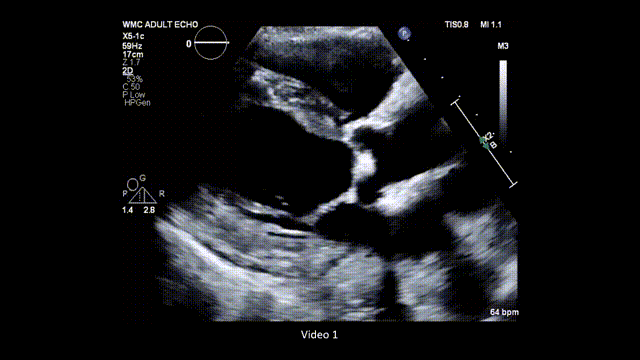

2、 在胸骨旁长轴切面放大(zoom)主动脉瓣(AV)和二尖瓣结构,分别采用普通二维和彩色多普勒模式进行评估(图3,视频2)。

图3. 胸骨旁长轴切面放大图像(普通二维和彩色多普勒对比)

胸骨旁长轴切面下主动脉瓣的放大图像,分别展示使用普通二维和彩色多普勒的情况。缩写同图2。

视频2. 胸骨旁长轴切面应用彩色多普勒(彩色与二维灰阶对比模式),评估主动脉瓣是否存在反流及主动脉瓣狭窄时典型的彩色镶嵌血流模式。